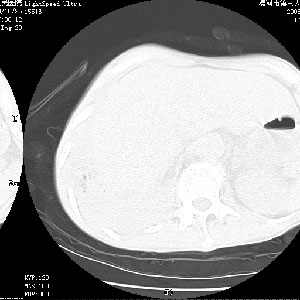

m 老年 发烧、呼吸困难,慢支、肺气肿多年;记的那次是下午大概17:38做的,晚上窒息死亡。

上面的层面就慢性支气管炎肺气肿、肺大泡,别的没有什么、也就不传了。

当时我怀疑:1、阻塞性肺不张早期 2、肺脓肿早期,望老师们发表意见

病灶边缘清---多个含气小腔---近端未见通畅气管影-----支持-----慢性肺脓肿继发阻塞性肺不张

阻塞性肺不张原因-----脓液未排出

3、细支气管肺泡癌可以排除,病变以斜裂为界,呈大片状高密度影,内可见多发小气泡,表明有产气杆菌感染所致,内无明显的支气管“枯树枝征”表现,再结合其临床改变(细支气管肺泡癌临表表现重、影像表现轻)所以不符合细支气管肺泡癌(炎症型)的改变。

病变按肺叶分布,病变内可见多个小空腔影,未见充气支气管影,中间段支气管管腔肺窗示密度欠均匀,下肺支气管分叉处基底段支气管隐约可见,未见明显狭窄,中叶支气管通畅,

考虑:阻塞性肺炎伴小脓肿形成可能性大。(痰栓可能性大)

右下肺实变,内有弥漫分面小气泡而无支气管征,叶间裂前移,呈臌大之形,而无收缩之状,兼纵隔稍左行移,故。不支持不张,倒支持大叶肺叶,如楼上所说,小气泡不象残留之肺,不可以考虑产气菌感染吗。

阻塞性肺炎,肺脓肿形成。依据,右下支气管不通,大片实变形内可见小气泡。不支持肺不张。